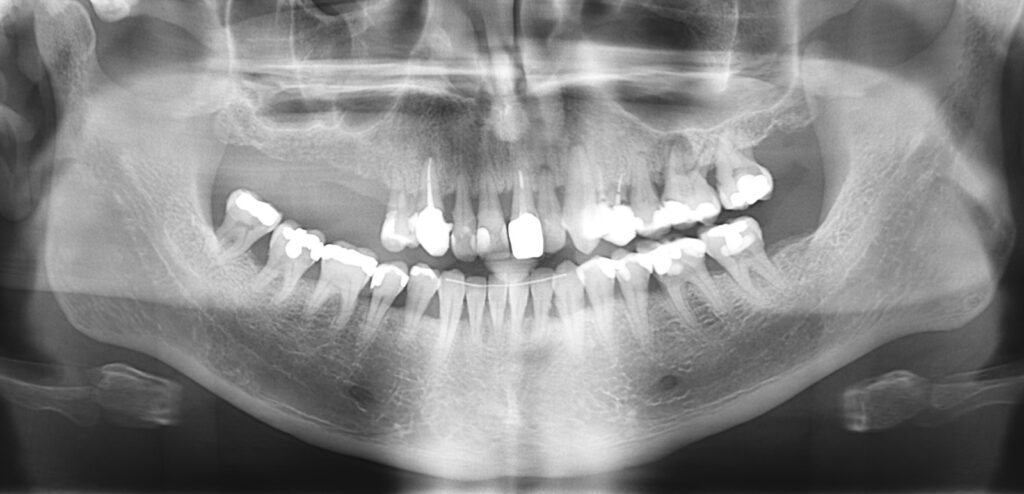

Caso clínico, Dr. José Amador Cabezas

Carga inmediata maxilar con cirugía guiada, registro fotogramétrico y provisionalización inmediata.

En este caso, el Dr. José Amador Cabezas aborda la rehabilitación completa de un maxilar superior comprometido por enfermedad periodontal avanzada, lesiones periapicales y múltiples restauraciones fallidas.

Tras la planificación protésicamente guiada y la colocación de implantes mediante cirugía guiada, se realizó el registro fotogramétrico con T-Marker sobre los Multi-Unit para capturar con precisión la posición real de los implantes y asegurar la pasividad de la estructura provisional.

Gracias a este flujo, el paciente pudo salir de la consulta con una prótesis fija inmediata el mismo día de la cirugía, iniciando así un proceso restaurador más preciso, más predecible y completamente integrado en el entorno digital.

La combinación de cirugía guiada, fotogrametría y carga inmediata permite un control preciso de la posición implantaria y una correcta pasividad protésica desde el primer día.